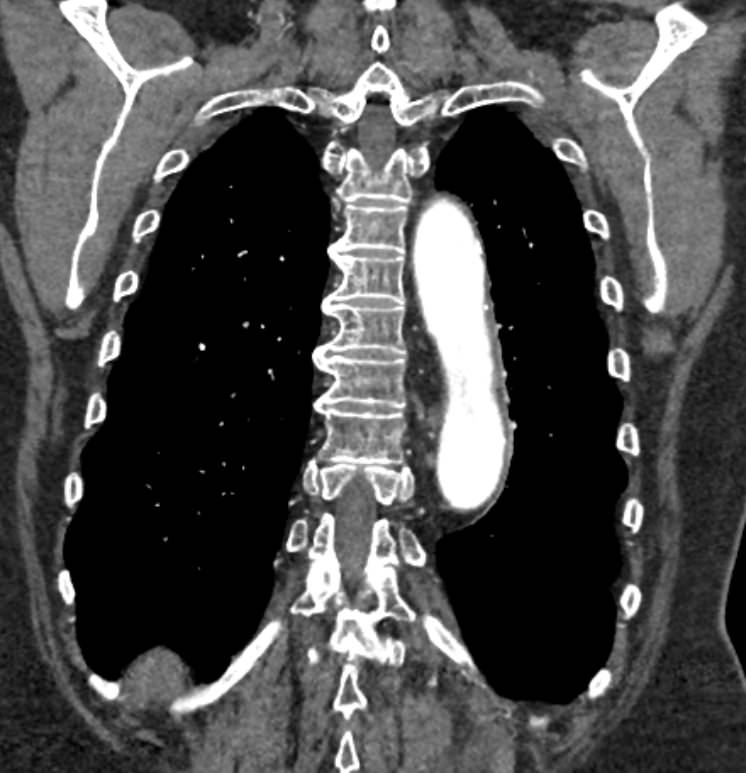

Грудная аорта делится на несколько отделов – восходящий отдел аорты, дуга аорты и нисходящий отдел. Корень аорты отходит непосредственно от левого желудочка, в его состав входят синусы Вальсальвы от которых берут начало коронарные артерии. После корня, прослеживается тубулярная часть восходящего отдела аорты, которая переходит в дугу аорты.

Дуга аорты дает начало брахиоцефальным артериям, которые питают головной мозг и верхние конечности. Затем следует нисходящий отдел аорты, распространяющийся через отверстие в диафрагме. От грудного отдела аорты отходят висцеральные артерии, кровоснабжающие органы средостения: бронхиальные, пищеводные, перикардиальные, медиастинальные артерии.

При истончении стенки аорты или ее ветвей формируется аневризматическое расширение участка сосуда, которое долгое время может никак себя не проявлять. Симптомы часто появляются при развитии осложнений – расслоения аневризмы (при разрыве внутренней оболочки сосуда и возникновения внутристеночной гематомы), разрыве аневризмы. Эти угрожающие жизни состояния можно избежать при своевременном выявлении аневризмы и проведения хирургического лечения.

Одним из информативных методов диагностики сосудистой патологии является мультиспиральная компьютерная томография грудной аорты и ее ветвей (КТ-ангиография). Метод сканирования при помощи рентгеновских лучей и цифровой обработки данных позволяет получать послойные снимки сосудов и трехмерные реконструкции сосудистой системы в мельчайших подробностях.

Для того, чтобы качественно визуализировать сосудистую систему КТ-ангиография предусматривает в обязательном порядке применение контрастного усиления. Йодсодержащее контрастное вещество вводится пациенту внутривенно и, благодаря способности контраста поглощать рентгеновские лучи, ярко контрастирует сосудистую систему на фоне окружающих тканей.

КТ-ангиография позволяет диагностировать аневризмы аорты, сосудистые аномалии развития, воспалительные изменения стенок сосудов, пристеночные тромбы, сужения просвета сосудов за счет сдавления извне близлежащими опухолевыми образованиями.